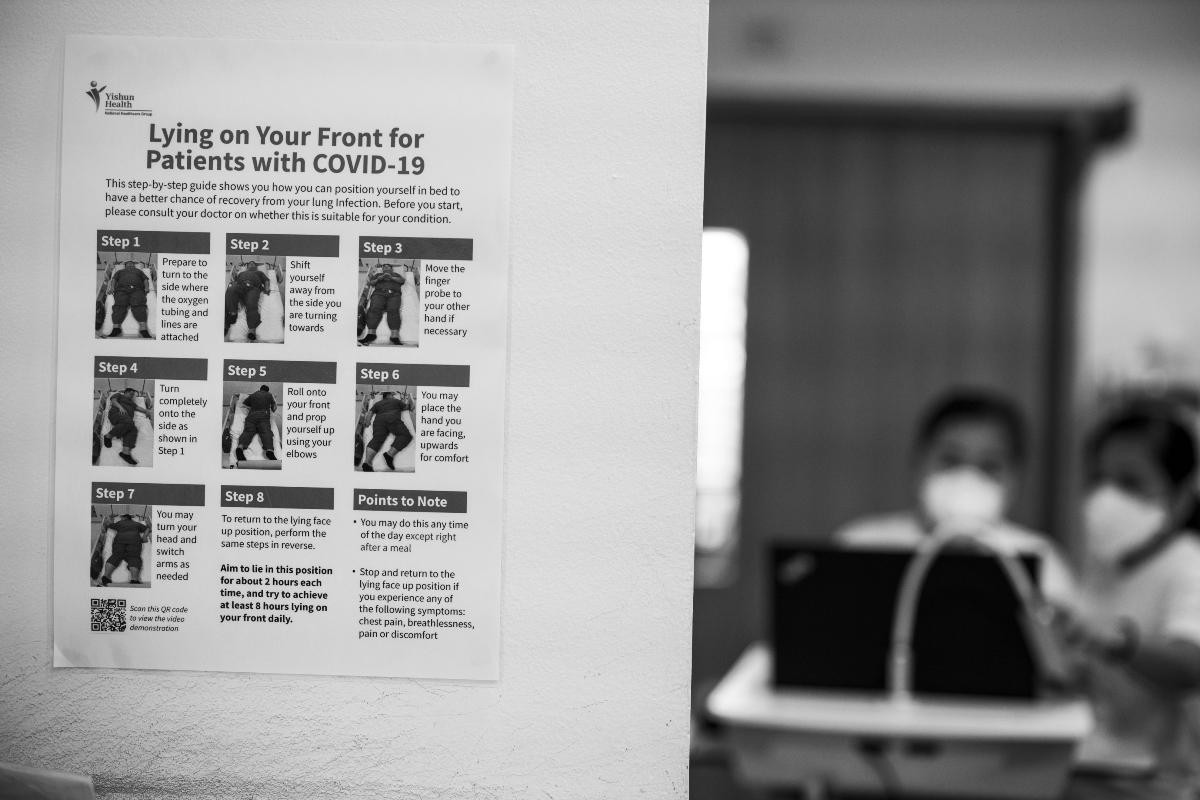

With this series of 32 photographs, Bob Lee documented the daily routines of two Senior Staff Nurses at Khoo Teck Puat Hospital, Christina Wong and Rawaida binte Mohamed Aron, during the circuit breaker lockdown in Singapore during the COVID-19 global pandemic. The photographs follow both nurses from the start to the end of their shifts, giving us a glimpse into a day in the life of a frontline worker.